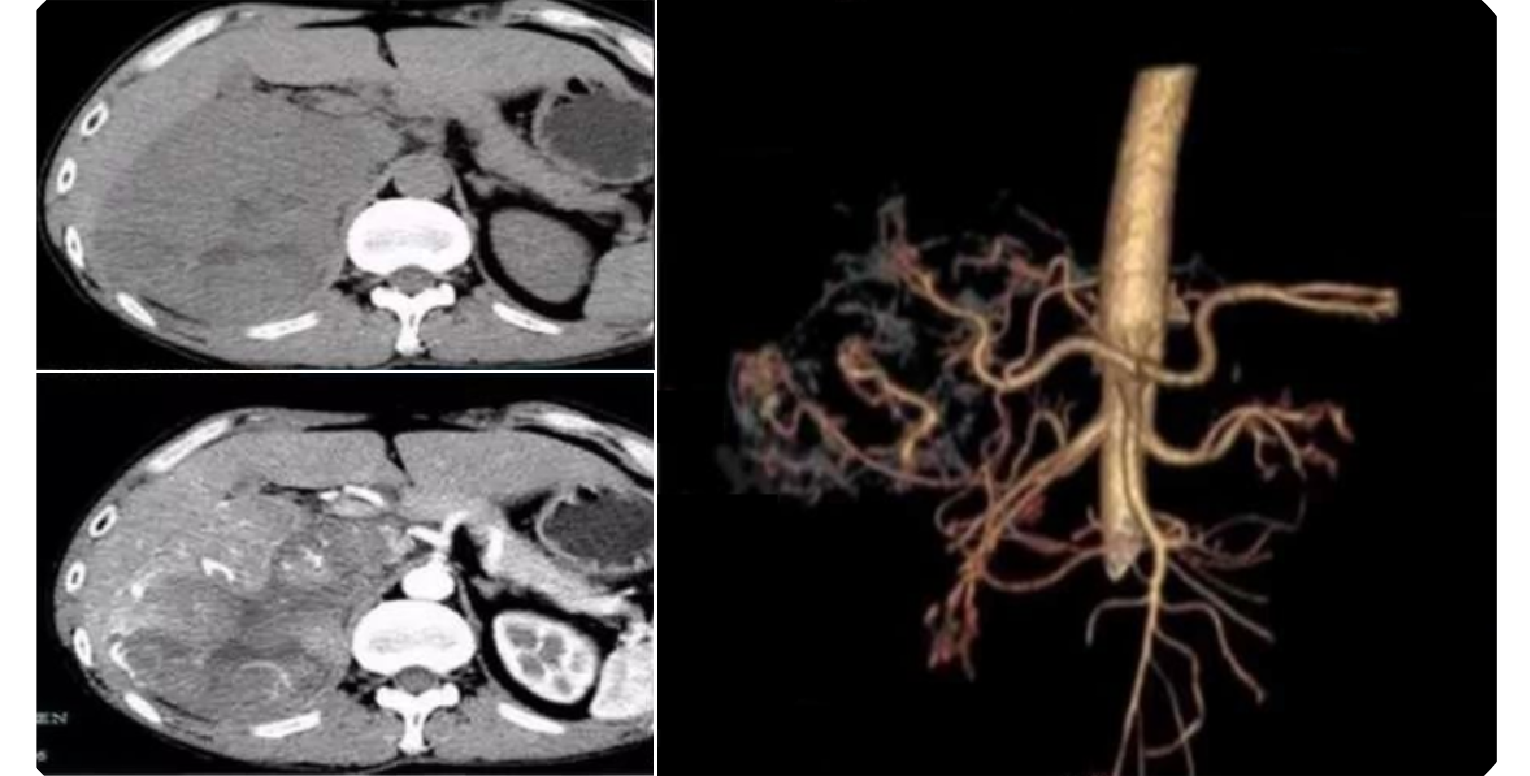

11b77622e265a21ed90c136aff4489c2.png 病例 42:左侧腹膜后副神经节瘤  62岁女性左侧腹膜后大肿块,边界不清,密度明显不均匀,内可见囊性坏死区及粗钙化灶,增强扫描可见实变区明显强化,中心囊性区未见强化。